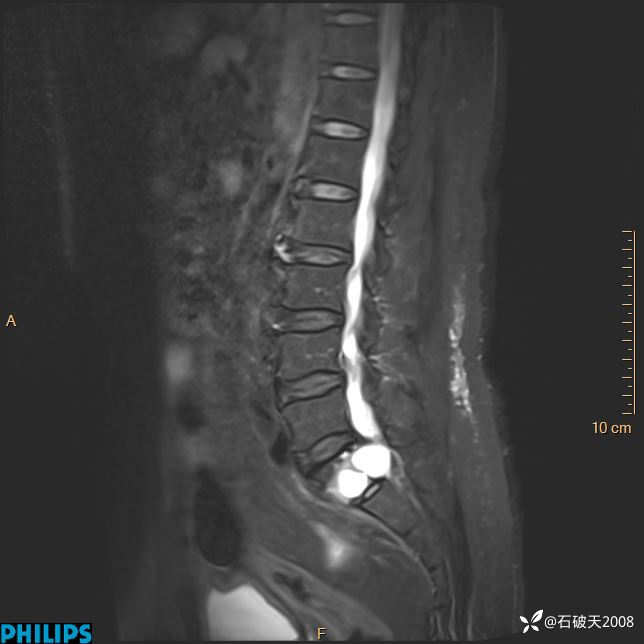

2023年3月份MRI影像

DWI